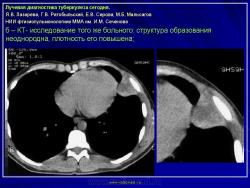

Лучевая диагностика туберкулеза сегодня

Я.В. Лазарева, Г.В. Ратобыльский, Е.В. Серова, М.Б. Мальсагов

НИИ фтизиопульмонологиии ММА им. И.М. Сеченова